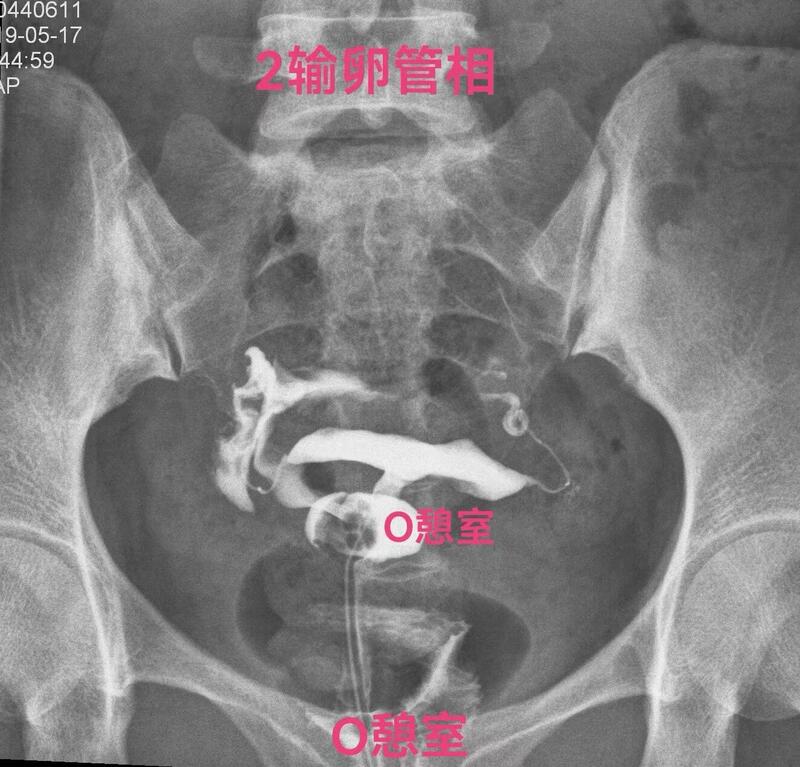

下面一例造影图就可以看直观看懂憩室导致经血流出不畅

弥散相子宫腔内造影剂完全流出来了,憩室内还有较多造影剂充满憩室腔。月经血流出相仿。